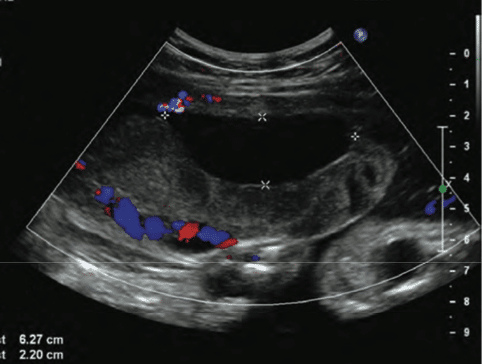

Ultrassom mostrando área anecóica (escura) atrás da placenta, compatível com um hematoma em função do descolamento prematuro de placenta.